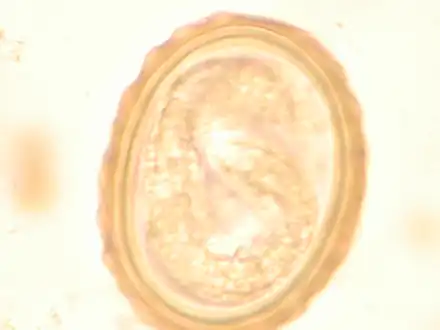

The larva of Ascaris lumbricoides developing in the egg

Ascaris egg, incubation process: The Ascaris egg incubation process consists of placing the egg in a controlled environment, at 26 °C (79 °F) during 28 days, in acidic conditions. This process allows for the evaluation of an egg to determine if it is viable or not.

Diagnosis

Most diagnoses are made by identifying the appearance of the worm or eggs in feces. Due to the large quantity of eggs laid, diagnosis can generally be made using only one or two fecal smears.[32] The diagnosis is usually incidental when the host passes a worm in the stool or vomit. The eggs can be seen in a smear of fresh feces examined on a glass slide under a microscope and there are various techniques to concentrate them first or increase their visibility, such as the ether sedimentation method or the Kato technique. The eggs have a characteristic shape: they are oval with a thick, mamillated shell (covered with rounded mounds or lumps), measuring 35–50 micrometer in diameter and 40–70 in length. During pulmonary disease, larvae may be found in fluids aspirated from the lungs. White blood cell counts may demonstrate peripheral eosinophilia; this is common in many parasitic infections and is not specific to ascariasis. On X-ray, 15–35 cm long filling defects, sometimes with a whirled appearance (bolus of worms).